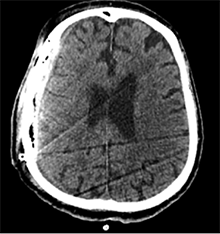

Po 2 savaičių pacientas rastas parkritęs kieme. Buvo matyti kraujuojanti žaizda. Pacientas pakartotinai hospitalizuotas į Neurochirurgijos skyrių. Atlikus GKT, nustatyta 25 mm storio hipodencinė juosta virš dešiniojo smegenų pusrutulio ir 8 mm vidurinių smegenų struktūrų dislokacija (VSD) į kairę (3 pav.). Įtariant lėtinę SDH dešinėje pusėje, pacientas reoperuotas, atliekant rekraniotomiją. Operacijos metu ant kietojo smegenų dangalo (KSD) rasta fibrino, jis pašalintas. Pravėrus KSD, rastas drumstas turinys, nesant aiškių pūlių, ir stora kapsulė. Gausiai praplauta šiltu fiziologiniu tirpalu subduraliai. Kaulinis lopas grąžintas (4 pav.). Po operacijos pacientas pradėjo skųstis stipriu galvos skausmu, tapo vangus. GKT pakartota. Įtarta empiema, nustatyti oro tarpai subduraliai, galvos smegenų VSD – 6 mm. Praėjus 12 dienų po antros operacijos, pacientas operuotas pakartotinai. Operacijos metu atlikta rekraniotomija. Epiduriniame ir subduriniame tarpuose rasta pūlių ir fibrino. Pūliai ir fibrinas pašalinti, paimtas bakteriologinis pasėlis. Žaizda gausiai praplauta šiltu fiziologiniu tirpalu. Kaulinis lopas negrąžintas, minkštieji audiniai susiūti (5 pav.). Po operacijos paciento būklė stabilizavosi. Bakteriologiniame pasėlyje negausiai užaugo E. coli, jautri ampicilinui. Nesant teigiamo efekto gydant ampicilinu, dar 2 savaites pacientui skirta gentamicino. Praėjus 3 savaitėms po trečios operacijos, pacientas perkeltas į slaugos ligoninę palaikomojo gydymo.

4 pav. Po antrosios operacijos (didžioji hematomos dalis pašalinta; VSD sumažėjo nuo 8 iki 5 mm)

5 pav. Po trečiosios operacijos (didžioji hematomos dalis pašalinta, nustatyta empiema, oro intarpų, VSD sumažėjo nuo 6 mm iki 4 mm)